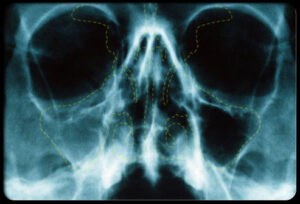

سینوزیت مزمن:

در این عکس MRI رنگی، نواحی آبی نشان دهنده پوشش مخاطی ضخیم شده در سینوس های فکی هستند. التهاب حفره سینوس اگر بیشتر از 3 ماه طول بکشد، سینوزیت مزمن است.اگرچه باکتری ها اغلب در سینوس های بسته شده تجمع می یابند، ولی در عفونت های باکتریایی تنها علت سینوزیت مزمن نیستند.اشکالات ساختمانی، حساسیت ها، پولیپ ها، نقائص سیستم ایمنی، و بیماری های دندانی هم ممکن است موجب مشکلات مزمن سینوس شوند.